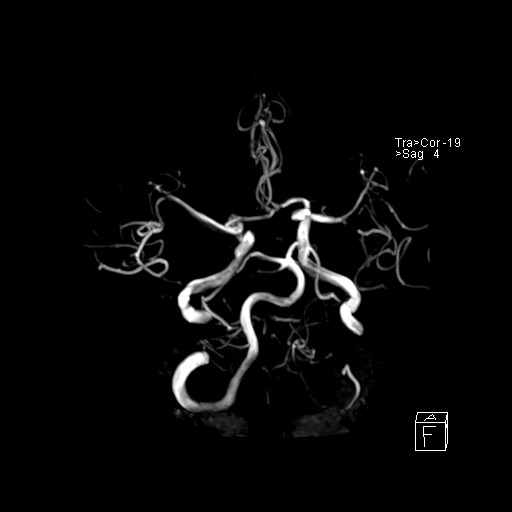

239716 - VILLANUEVA, WILLIAM A. - Number 1 |

239716 - VILLANUEVA, WILLIAM A. - Number 1 |